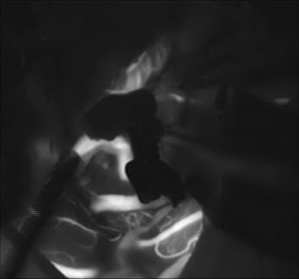

如图所示:原有血管血流清晰,被夹闭动脉瘤不显影

经科室讨论,神经外六科吴杰主任团队为解先生实施了手术,术中将动脉瘤与周围血管准确分离,并成功夹闭。术后复查CT,显示动脉瘤被夹闭,手术区域未见明显异常。